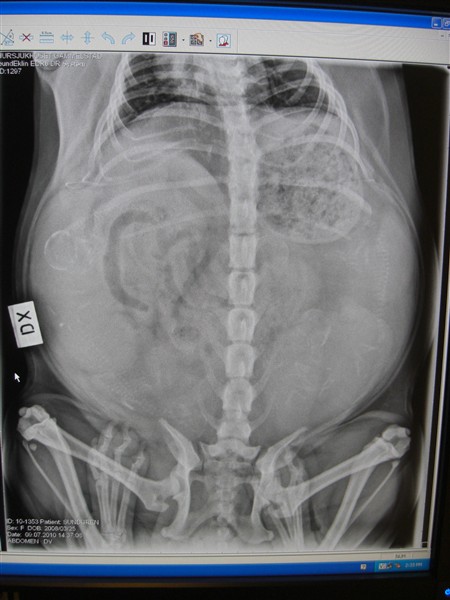

Och så till Doris...röntgat henne idag för att se hur många puppisar som finns där inne...och 5 små bäbismopsar finns det i magen

:) hoppas bara att allt med valpning ska gå bra:):)

Det är så varmt för henne nu och tungt med magen......